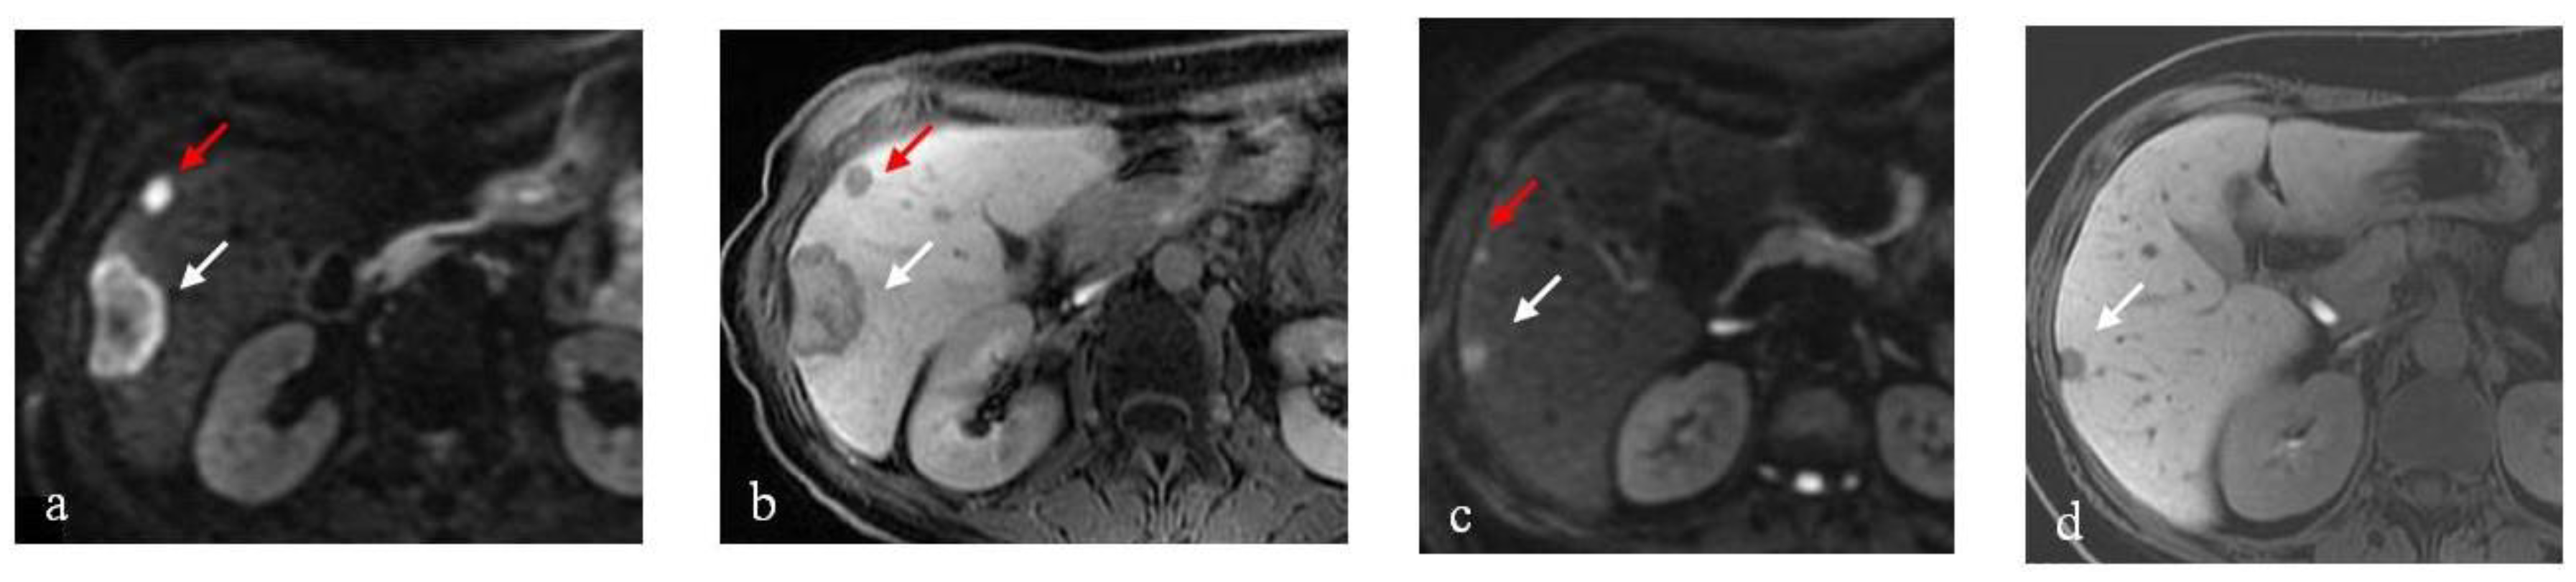

3.1. DLM Results

3.2. RTLM Results

3.3. SRLM Results